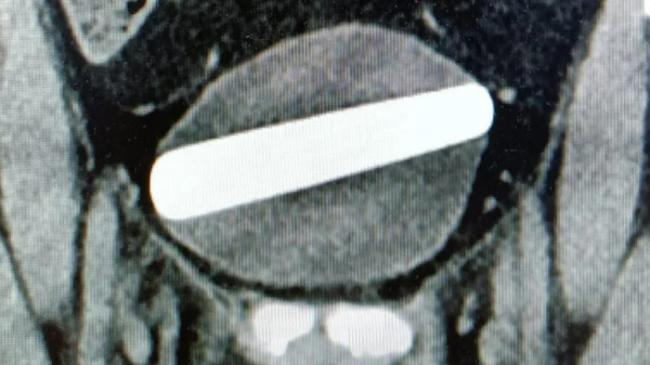

Yayınlanan rapora göre, kadın sürekli olarak yaşadığı mide ağrıları ile acil servise geldi. Bir ultrason testi ve röntgen çektikten sonra, mesanesine yatay olarak bir seks oyuncağının yerleştirildiği keşfedildi. Doktorlar seks oyuncağını çıkarmak için sistoskop adı verilen ince bir kamera kullanarak mesanenin içine bakma prosedürü olan sistoskopi yaptılar. Bu yöntemde idrarı vücuttan dışarı taşıyan tüpe bir sistoskop sokulur ve doktor veya hemşirenin içini görmesini sağlamak için mesaneye gönderilir. Prosedür başarılı oldu ve turist sorunsuz bir şekilde eve gönderildi.

Ameliyatı gerçekleştiren Prof. Boris Certin, “Mesaneye giren yabancı bir cisim deliğe neden olarak karın içine tehlikeli bir sızıntıya yol açabilir, bu nedenle kaybedecek vaktimiz olmadı. “Oyuncakların vajinaya sokulması da yırtıklara neden olabilir, bu da mesaneye sızmaya ve enfeksiyona neden olabilir. İnsanlara özel hayatlarında ne yapmaları gerektiğini söylemeyeceğiz ama seks oyuncakları kullanmanın tehlikelerine dikkat etmek önemlidir. Onları yerleştirildikleri şekilde çıkarmak her zaman mümkün değildir.”